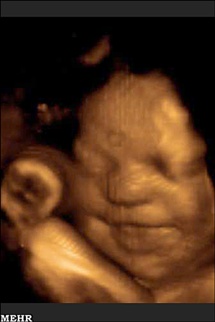

خنده ی جنین در شکم مادر + عکس

جنین پیش از تولد حرکت دادن اجزای صورت خود را آغاز می کند، بینی اش را چین می اندازد و یا ابروهایش را بالا می برد، حرکاتی که دانشمندان به تازگی دریافته اند با رشد روز به روز جنین پیچیده تر می شوند.

به گزارش خبرگزاری مهر، با اینکه دانشمندان از گذشته نیز می دانستند که جنین ها در دوران جنینی از بیان چهره برخوردارند و می توانند اندامهای چهره خود را حرکت دهند، مطالعه جدید، این حرکات بر روی چهره جنین ها را در طول زمان مورد بررسی قرار داده است.

به گفته محققان دانشگاه دارهام در انگلستان آنچه به تازگی کشف شده این است که پیچیدگی حرکات صورت جنین ها در طول زمان تا پیش از متولد شدن روز به روز افزایش پیدا می کند. محققان برای بررسی این روند از دو جنین از سن 24 تا 35 هفتگی تصویربرداری کرده و پیشرفت حرکات صورت آنها را تا زمانی که به ترکیبی از حرکات پیچیده مرتبط با بیانات قابل تشخیص چهره تبدیل شدند را مورد بررسی قرار دادند.

در پی ردیابی 19 حرکت در صورت جنین ها محققان بر روی حرکاتی متمرکز شدند که با بیان دو حالت، گریه کردن و خندیدن در ارتباط بودند. در طول زمان حرکات مرتبط با این دو حالت ترکیبهای پیچیده تری پیدا کردند.محققان برای تصویربرداری از جنین ها از سیستم تصویربرداری فراصوت چهار بعدی استفاده کردند تا بتوانند حرکات مرتبط با بیان چهره را در دو جنین دختر مورد بررسی قرار دهند. در سن 24 هفتگی جنینها حرکتهای ساده ای مانند بازکردن لبها را انجام می دادند. با گذشت چند هفته جنینها ترکیب حرکات را آغاز کردند و هنگام بازکردن لبها، بینی خود را نیز چین می دادند. در هفته سی و پنجم ترکیبی از سه یا چهار حرکت مرتبط با دو بیان چهره (گریه و خنده) در جنینها مشاهده شد.محققان می گویند این حرکات در چهره جنین ها به این معنی نیست که احساس خاصی به جنین ها دست داده است، زیرا جنین ها هنوز از قدرت کافی برای داشتن احساسات برخوردار نیستند. به علاوه به نظر می آید این حرکات نوعی آماده سازی جنین برای ورود به جهانی اجتماعی باشد، جایی که باید با دیگران ارتباط برقرار کنند. جنین ها همچنین انگشت شست خود را به دهان برده و می مکند و حرکاتی مبنی بر تنفس کردن از خود نشان می دهند که هر دوی این حرکات زمینه ساز رفتارهایی هستند که پس از متولد شدن برای ادامه بقای آنها حیاتی به شمار می روند.بر اساس گزارش لایو ساینس، محققان قصد دارند در آینده بر روی حرکات صورت جنین ها که با حالتهای عصبانیت، خنده و غمگینی در ارتباط هستند متمرکز شوند.